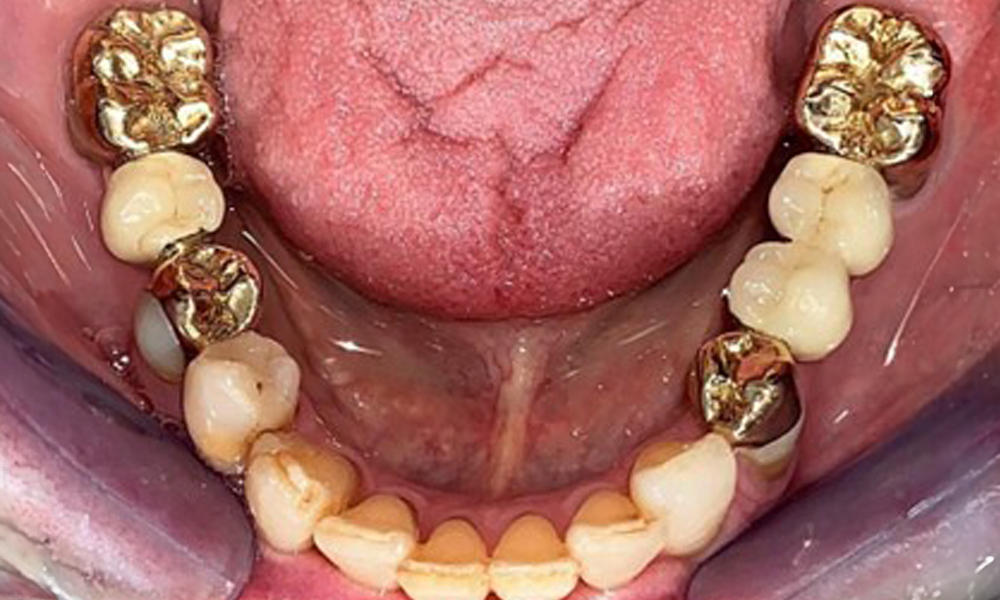

Okklusalansicht: Oberkiefer mit herausnehmbarer, gaumenfreier Prothese.

Abb. 3 Okklusalansicht: Oberkiefer mit herausnehmbarer, gaumenfreier Prothese.

Die Patientin wurde vor über 25 Jahren mit einer kombinierten herausnehmbare Implantat-Teleskopprothese im Oberkiefer versorgt (Abb. 1, Abb. 2, Abb. 3) und ist sehr glücklich über ihren Zahnersatz. Im Unterkiefer hat die Patientin einen suffizienten festsitzenden Zahnersatz. (Abb. 4)